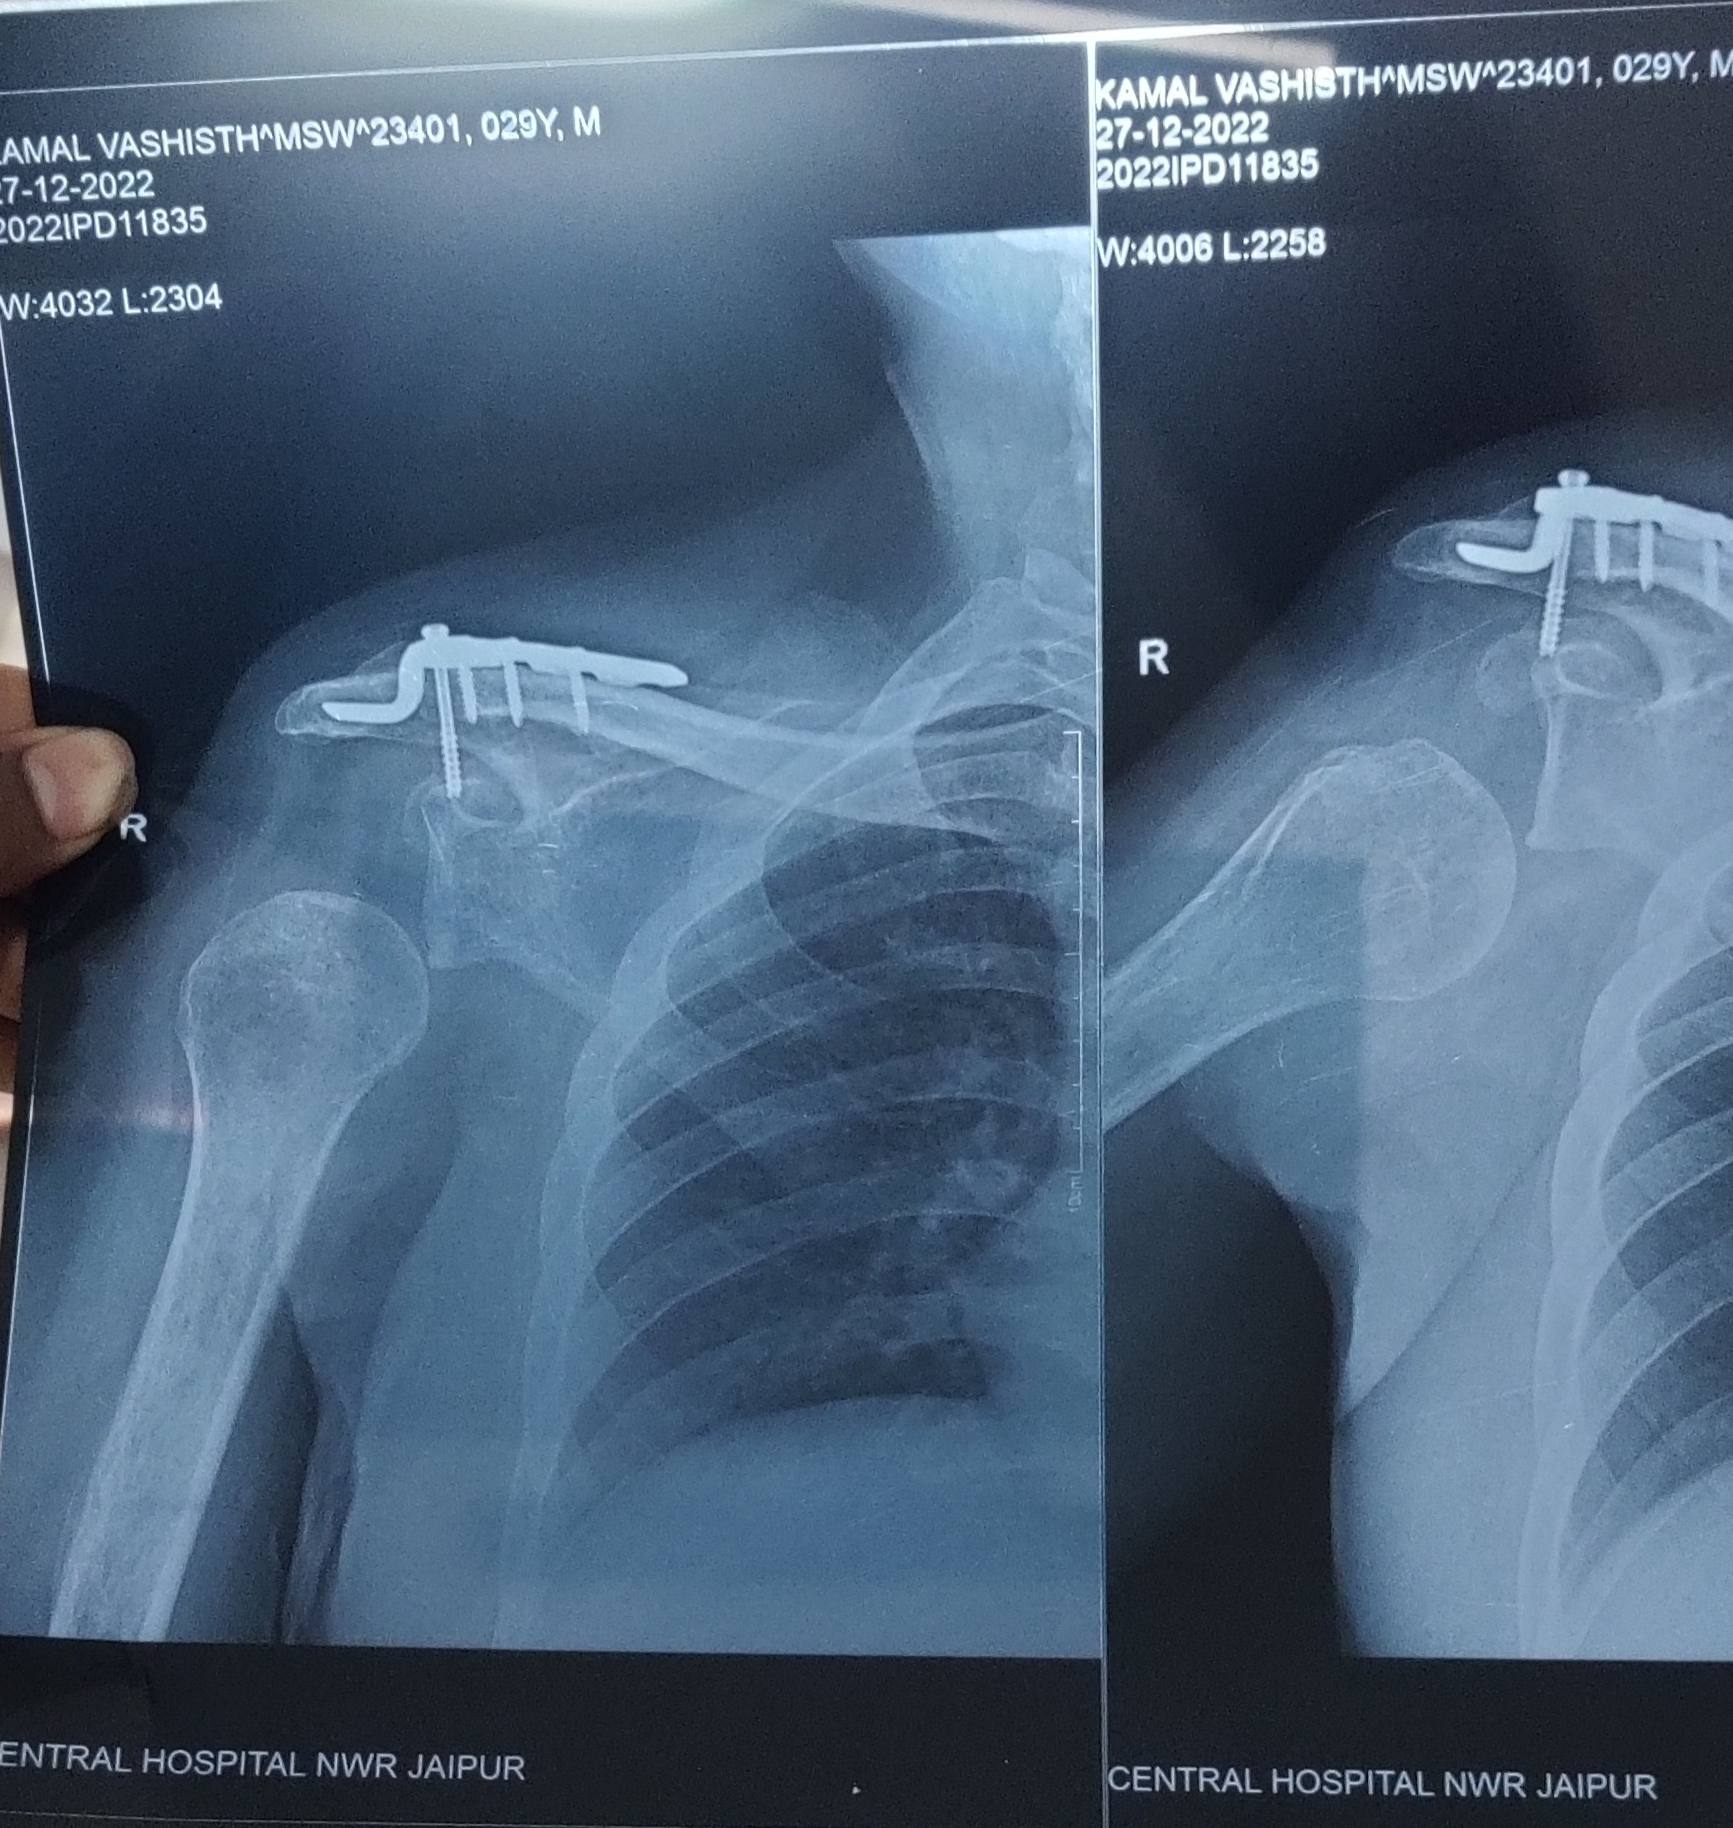

Sir mera accident hua tha 9 may ko mere haat aur pair mai lagi thi.... Mere kandhe ka maas fat gaya tha aur ek plat bhi lagayi thi aur 3 month baad mera brachial plexus ka operation bhi hua h... Meri fingar rist chal rhi h par shoulder ki bone niche h.... Plzzz sir meri help kare